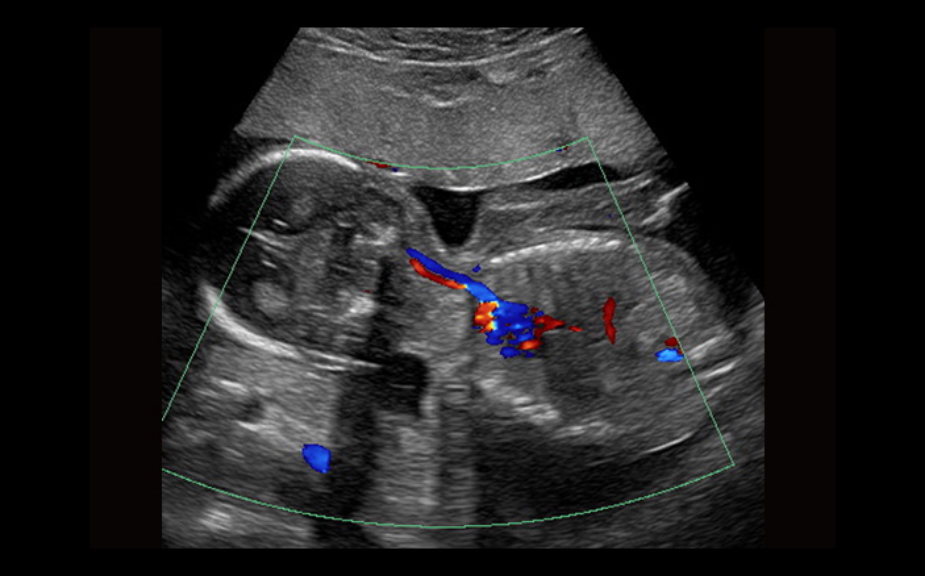

Equipped with patented, software based ZONE Sonography? Technology (ZST), the Z.One PRO provides optimally detailed B-mode and Doppler imaging for patients, regardless of body habitus, helping assure a reliable diagnosis.

Throughout a wide range of applications, the Z.One PRO is the ultrasound solution for your demanding clinical challenges.

- Unsurpassed image quality across all applications

The Z.One PRO is powered by ZONE Sonography Technology, an innovative and proprietary image formation architecture that acquires and processes acoustic data up to ten times faster than conventional beamforming methods.

The Z.One PRO ultrasound imaging platform offers a complete family of lightweight transducers that feature both extended broadband capabilities and multi-frequency flexibility delivering exceptional clarity and enhanced detail resolution even at the deepest depths. The C4-1 transducer can penetrate throughout the field of view while maintaining exception spatial and contrast resolution.